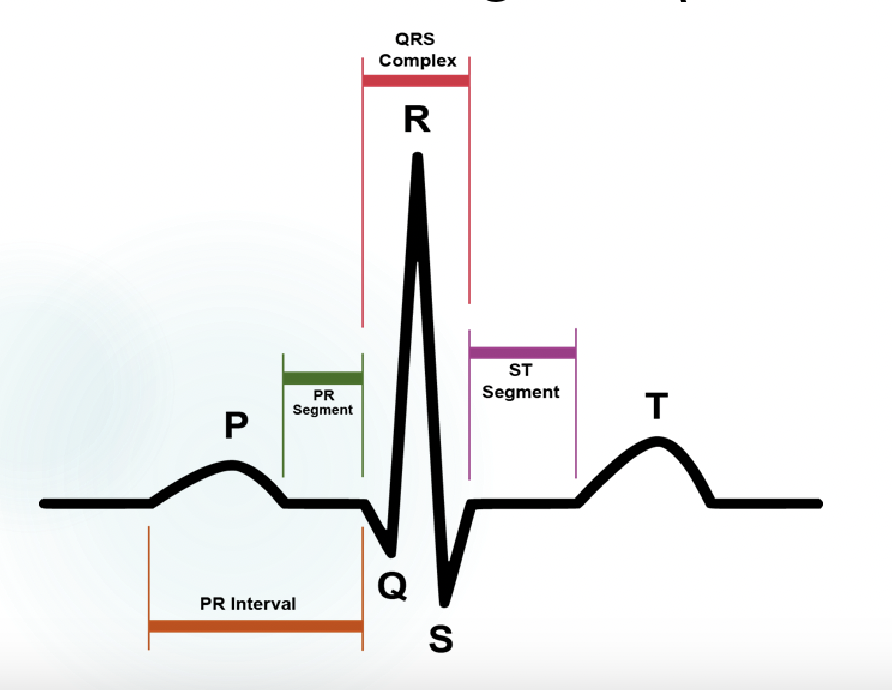

explain what is happening at P, QRS, and T

-p wave: atrial contraction

-QRS complex: ventricular contraction

T wave: ventricular relaxation